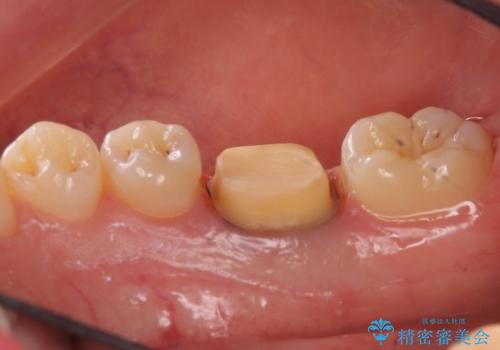

- 樹脂をやり替えたいとのことで来院されました。

特に大きな虫歯もありませんでしたが、残った歯が薄かったためクラウンでの修復処置を行いました。

インレーにすると残った歯が薄くなってしまう場合は術後の破折リスクが高いためクラウンで修復することがあります。